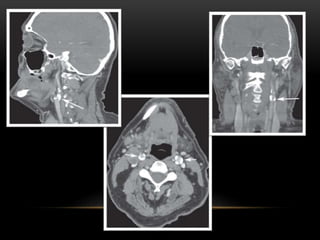

RADIOGRAPHIC FEATURES

• On the panoramic film,

tonsilloliths appear as

single or multiple

radiopacities that overlap

the mid portion of the

mandibular ramus in the

region where the image of

the dorsal surface of the

tongue crosses the ramus

in the palatoglossal air

spaces.

• It appears as clusters of

multiple small ill-

defined radiopacities.

This may vary from 0.5

cm to 14.5 cm in

diameter.

• The radiopacity is of

the same density as

that of cortical bone,

and a little more

radiopaque than

cancellous bone.

On axial computed tomographic (CT) images, they appear in the soft

tissue medial to the mandibular ramus and next to the lateral wall of

the oropharyngeal air space.